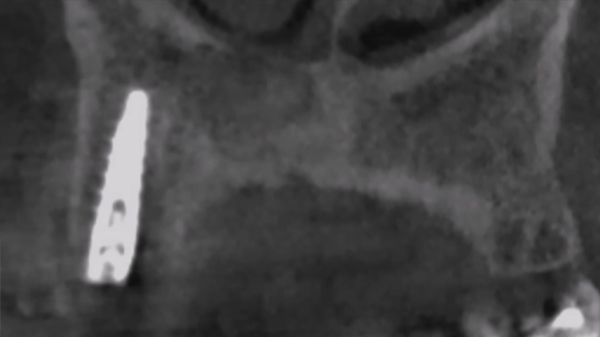

Il Magnetic Mallet è uno strumento totalmente innovativo destinato alla chirurgia odontoiatrica ed implantologica, che trova le sue principali applicazioni nel rialzo del seno mascellare, nei protocolli di compattazione ed espansione ossea verticale ed orizzontale, e più in generale in tutti i casi in cui normalmente si utilizza il martello chirurgico.

L’apparecchio sfrutta l’impatto elettromagnetico, che permette di avere una forza d’urto di alta intensità e di brevissima durata tale da ottenere la deformazione plastica dell’osso, ma senza propagarsi in tutta la scatola cranica, come avviene usualmente con i colpi del martello chirurgico. È per questo che l’utilizzo del Magnetic Mallet previene nel paziente la cosiddetta sindrome vertiginosa parossistica benigna, ossia la sintomatologia postoperatoria di tipo vertiginoso.

Il manipolo ergonomico del Magnetic Mallet si utilizza con una sola mano e gli impulsi vengono impartiti con un comando a pedale, lasciando l’altra mano libera consentendo una maggiore visibilità in campo operatorio. I numerosi clinici che hanno già adottato questo strumento nella quotidianità della pratica implantologica riferiscono tutti la medesima sensazione di estrema precisione nella fase di penetrazione dei bone expander. Infatti un osso con un guscio molto corticalizzato ed un interno scarsamente mineralizzato per sua natura solitamente devia il corso dell’osteotomo manuale quando esso passa da una interfaccia all’altra. Inoltre la stessa dinamica del martello chirurgico talvolta trasmette all’osteotomo forze non esattamente ortogonali al piano di lavoro, causando accidentali spostamenti d’asse che in mani non esperte sono di difficile gestione.